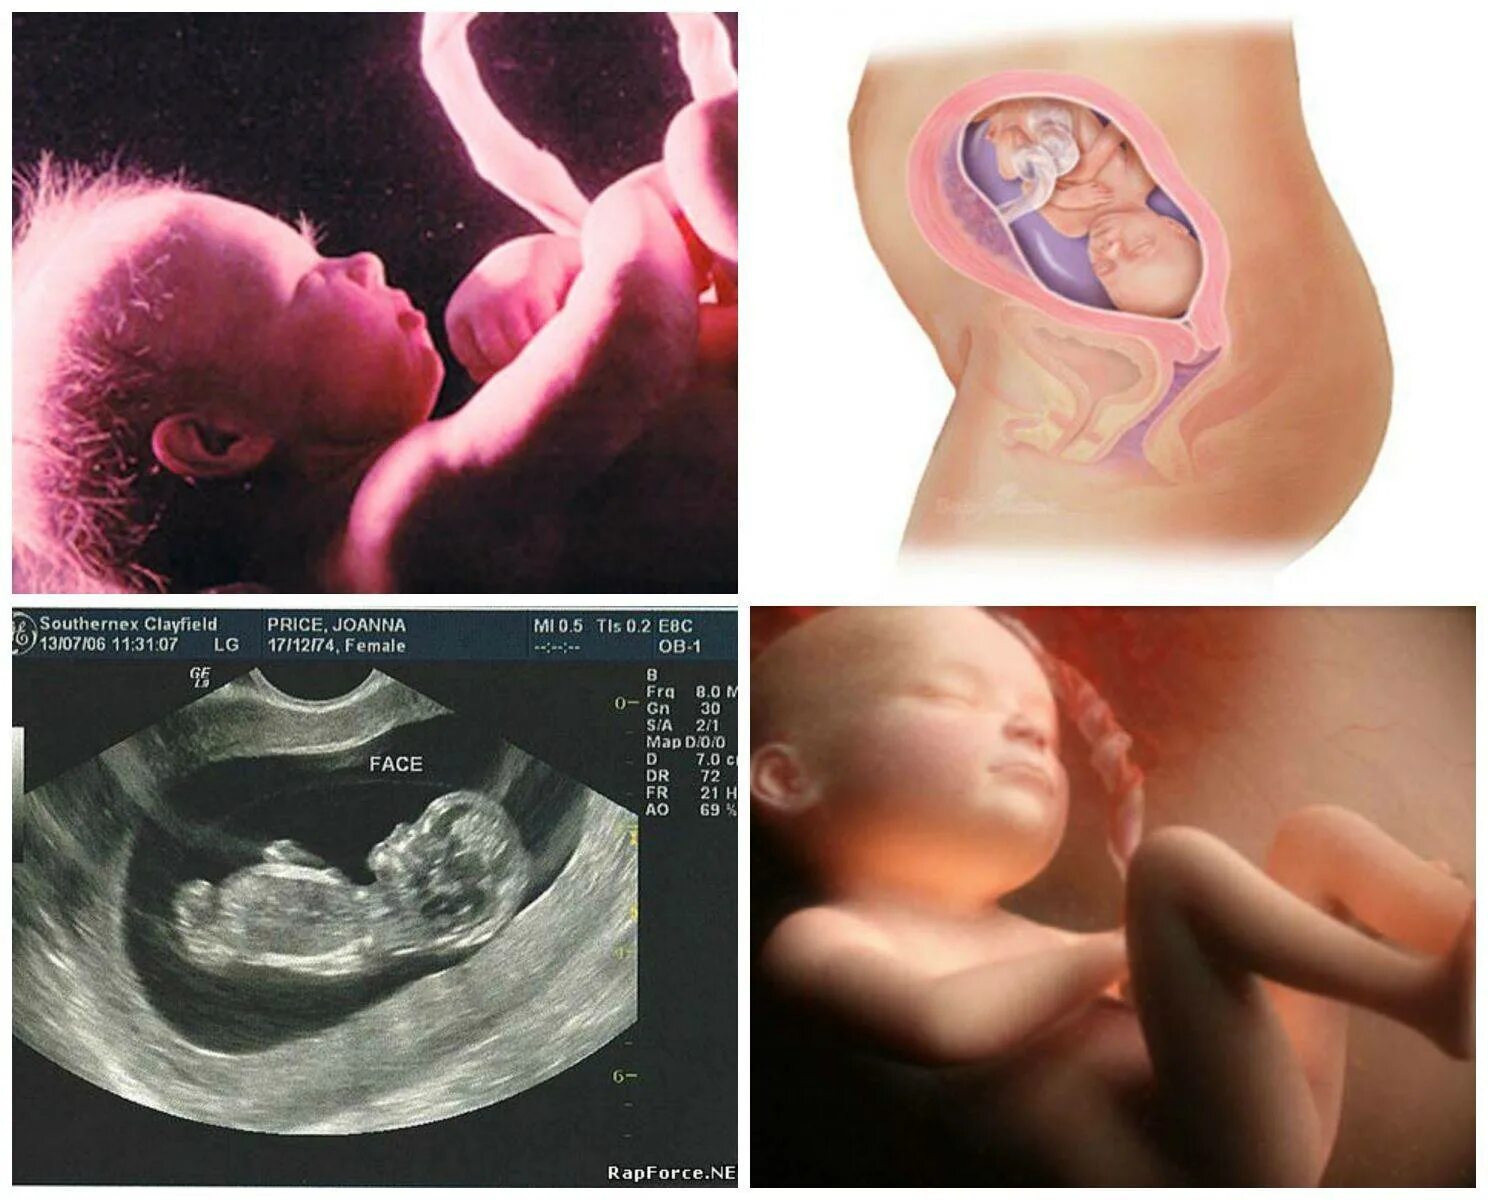

Ощущения 27 неделя